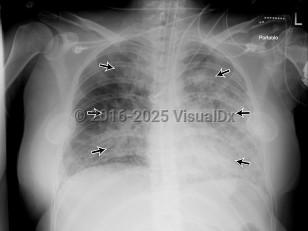

Acute respiratory distress syndrome

Clinically, ARDS is characterized by decreased compliance in the lungs ("stiff lungs"). On a microscopic level, it involves alveolar edema due to increased permeability from membrane destruction ("leaky capillaries") as well as neutrophil infiltration, which can lead to activation of a localized inflammatory response. Once the alveoli are damaged, they will start to collapse, leading to atelectasis derecruitment of the lung. Although mechanical ventilation is the mainstay of treatment, it can be challenging and must be done carefully and within specific parameters, as repetitive re-expansion and collapse of the alveoli can lead to mechanical injury known as atelectrauma and the elevated mean airway pressures or excess tidal volumes in the setting of decreased lung compliance result in alveolar barotrauma / volutrauma.